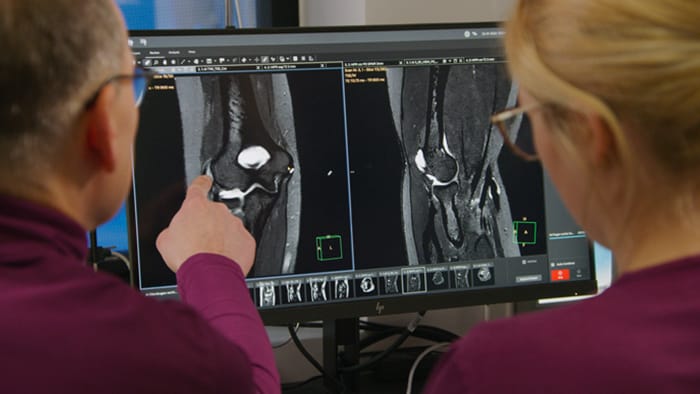

Dr. Tobias Schröter, MD, has been a radiologist since 2000. After running a 24/7 radiology practice for 16 years, he took over MRT-Praxis Potsdam, specializing in MRI diagnostics. “After the takeover, I completely redesigned the premises and exchanged the older MRI machine for a 1.5T Philips Ingenia Ambition S with sealed magnet.” Recently, the MRI Practice in Potsdam acquired AI-based Philips SmartSpeed of which Dr. Schröter has found that it makes a significant difference. “We had already been using Compressed SENSE from Philips to accelerate our cartesian scans and increase throughput. SmartSpeed now allows us to further reduce scan times and artificial intelligence (AI) makes the image quality even better compared to images we acquired using Compressed SENSE.” Dr. Schröter now uses SmartSpeed for 2D and 3D sequences in all anatomies. “I am astonished at the great potential of SmartSpeed, especially because 3D imaging in MSK is becoming feasible now. I can get very good image quality in very short scan time.” He also uses SmartSpeed for patients that cannot hold still, without worrying about needing re-scans. And it can also be used for patients with implants. “Besides the fast scanning, we now have the advantage of fast image reconstruction, so that we can already look at images while the scanning is still ongoing.”

Then, because the computing capacity is so large, we have the images immediately available on the large screen. Higher resolution is very valuable. From the high-resolution 3D sequences, excellent multiplanar reconstruction can be obtained. This makes it easier and faster for us to diagnose and create reports. And while the patient is still lying in the magnet, we can already view the images and make a diagnosis. When the patient comes out, I can immediately ask whether what I see corresponds to the symptoms.”

“The big 27-inch 4K high resolution screen makes a total difference. It shows the large planning images with much higher resolution than we were used to. Anatomic landmarks can be more easily identified, which advances the process. Now it is much easier and faster to plan the new sequences and it’s easier for us to find lesions,” says Dr. Schröter.

Another important part of MR Workspace is the graphics processing unit (GPU), which allows on-the-fly reconstruction times for images acquired with SmartSpeed. “In addition to seeing razor-sharp images on the large 4K monitor, we also have better and faster reconstruction of the images. Using this extremely high resolution, we sometimes have sequences with up to 800 individual images. The GPU then manages to convert them in a matter of seconds into multiplanar reconstructions. Very impressive.”